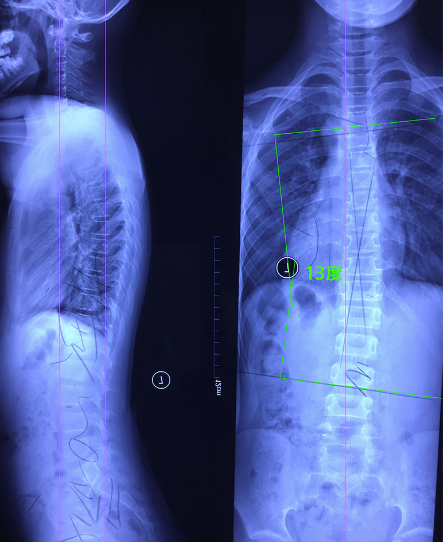

12岁西安女孩脊柱侧弯支具矫形一例报告